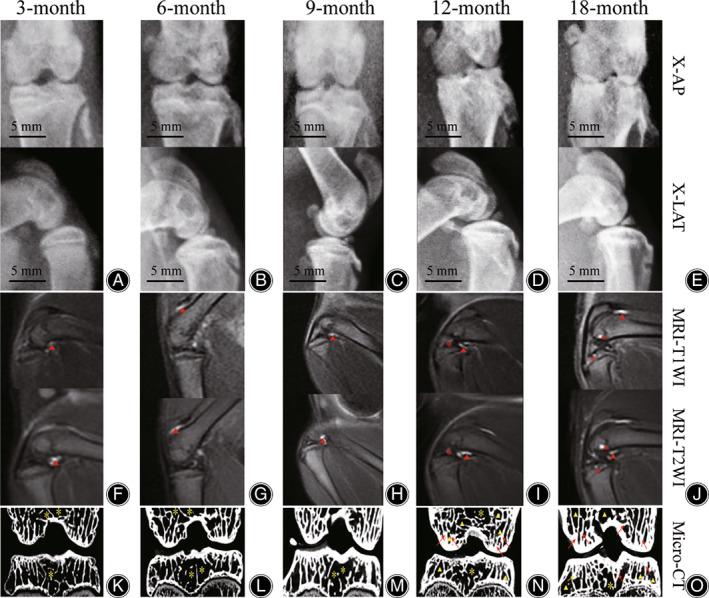

Male Dunkin-Hartley guinea pigs were selected and divided into groups of 3, 6, 9, 12, 18 months old by age, 10 in each group. All knees underwent imaging examination including X-ray, Micro-CT and MRI. Observed the imaging findings with the use of Kellgren-Lawrence (K-L) classification and knee osteoarthritis MRI scores. Measured the IOP of distal femur (DF) and proximal tibia (PT) in each group, and observed the differences of bilateral tibiofemoral articular cartilage in histological and immunohistochemistry, staining results were evaluated by using Mankin's score. Analysis of variance (ANOVA) and t-tests were used to compare the differences indicators between groups.

With the increase of age, changes in X-ray, Micro-CT and MRI imaging findings and pathological staining results of articular cartilage in all stages were consistent with the changing of degenerative KOA process. The IOP of DF and PT increased gradually with age, and reached its peak in 12-month age group, and then gradually decreased, there was a statistically significant difference of IOP between each group. The IOP of DF was slightly higher than that of PT, but the difference was not statistically significant.